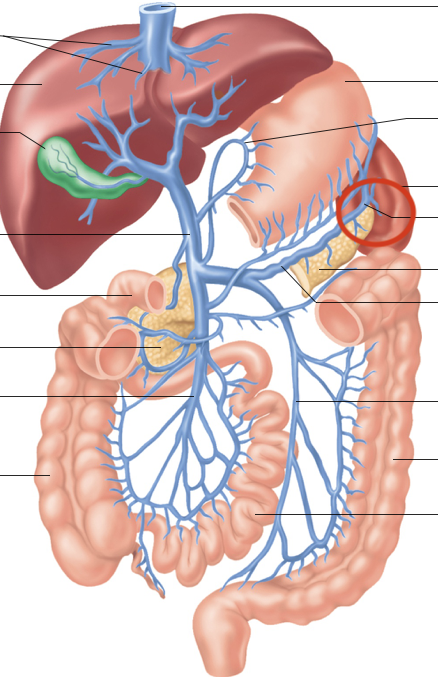

Hepatic Portal System (illustration)

hepatic portal vein

superior mesenteric-small intestine, first half colon

gastric-stomach

splenic-spleen and pancreas

inferior mesenteric-second half colon

hepatic veins